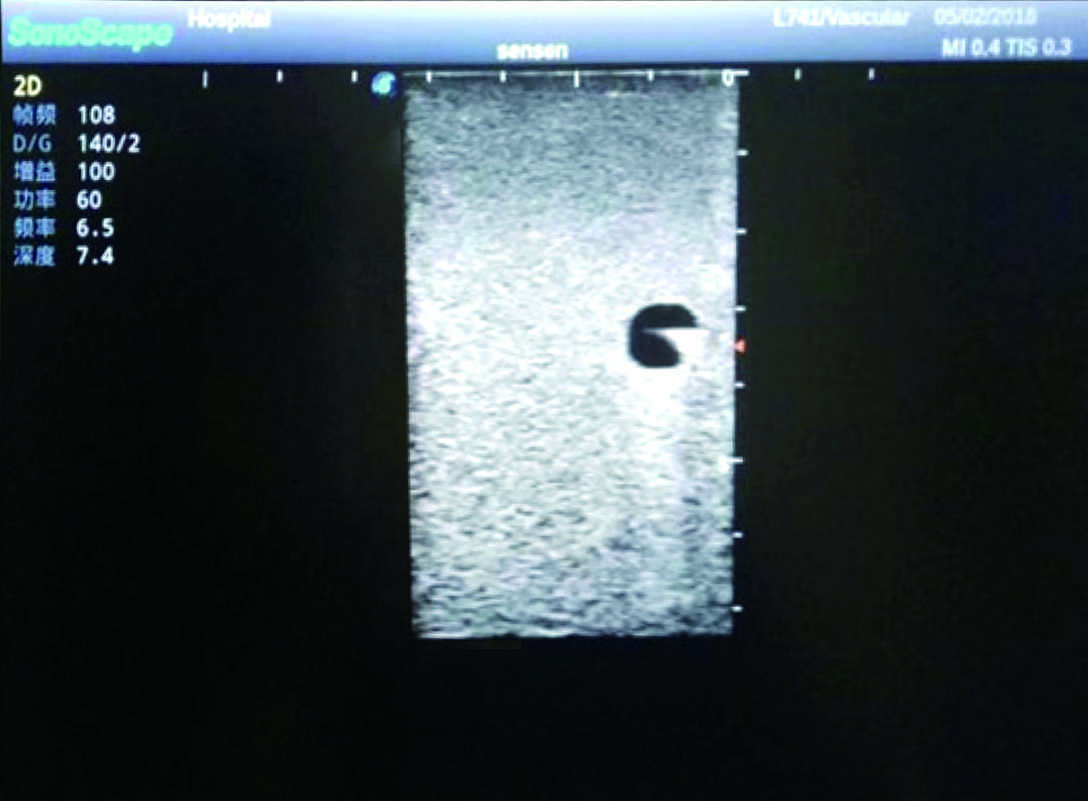

3)   Clear and real images of the tissues and organs (basilic vein and superior vena cava)

4)   When conducting vascular puncture, the piercing can be truly felt, and venous blood outflow can be seen

5)   Observe the guide wire marches